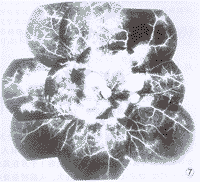

例3 女,16岁,主诉军训后疲乏,双眼视物不清一周。于1996年10月3日来眼科门诊检查,视力双眼0.1,眼前节正常。散瞳检查眼底:视乳头色稍淡尤以颞侧明显,边界清楚,黄斑水肿,动脉稍细,静脉扩张纡曲,后极部视网膜散在大量棉絮样斑无出血(图3,4)。疑为胶原血管性眼底病变,转内科检查。全身检查:血压130/90 mmHg,双侧面颊对称性红斑,红细胞沉降率44 mm/1h,抗核抗体阳性,血清球蛋白增高为44 g/L,肝功异常,诊断:SLE。1997年12月29日门诊追踪检查,视力右眼0.05,左眼0.1,双眼前节正常。眼底右眼视乳头色苍白,边界清楚,黄斑中心凹光反射消失,色素沉着,视网膜动静脉细有白鞘,从视乳头上有新生血管机化膜并沿四支大血管走行。视网膜后极部有少量点状出血(图5)。左眼视乳头色淡白,边界清楚,黄斑中心凹光反射消失并往上移位。动脉细有白鞘,静脉血管纡曲管径粗细不匀,并有新生血管膜形式。视网膜散在点片状出血(图6)。FFA双眼动静脉血管管径细,粗细不匀晚期管壁染色,视网膜周边3600均有大片毛细血管闭塞区, 呈现弱荧光。围绕视乳头3600距视乳头0.5~8.0 PD范围有大量新生血管,呈现多簇大小不等的强荧光团(图7,8)。诊断:双眼SLE视网膜血管炎合并新生血管;视神经萎缩。嘱查视野并作激光光凝,但患者家在农村未再复诊。

图3,4 例3患者双眼眼底普通像。后极部视网膜大量棉絮样斑 图5 例3患者右眼眼底彩色像。视盘色苍白,从视盘上有新生血管机化膜沿四支大血管走行 图6 例3患者右眼眼底彩色像。视盘色淡白,后极部视网膜有多数新生血管形成 图7 例3右眼眼底荧光血管造影像。视网膜周边部大量无灌注区,围绕视盘有大量新生血管产生的荧光素渗漏 图8 例3左眼眼底荧光血管造影像。视网膜周边部大量无灌注区,后极部多数新生血管渗漏,下方有视网膜前出血(箭头)